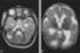

Familial diffuse cortical dysplasia

Pachygyria